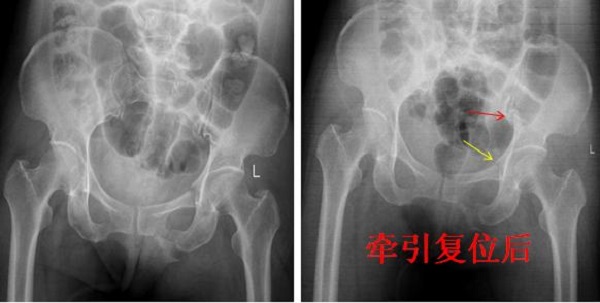

近日,陕健医二一五医院骨科医院创伤骨科收治了一例54岁女性骨盆骨折患者,查体发现左髋关节因疼痛活动受限,骨盆挤压分离试验(+),X线及CT检查提示骨盆骨折,骨盆骨折Young & Burgess 分型为LC-II型骨折,术前经左下肢骨牵引,手法协助闭合复位拍片可见骨盆骨折复位良好,郭永良主任医师详细了解患者受伤机制,根据复位效果及骨折类型制定了微创化手术治疗方案,即LC-II通道螺钉+耻骨髓内针的微创化治疗。

术前X线: